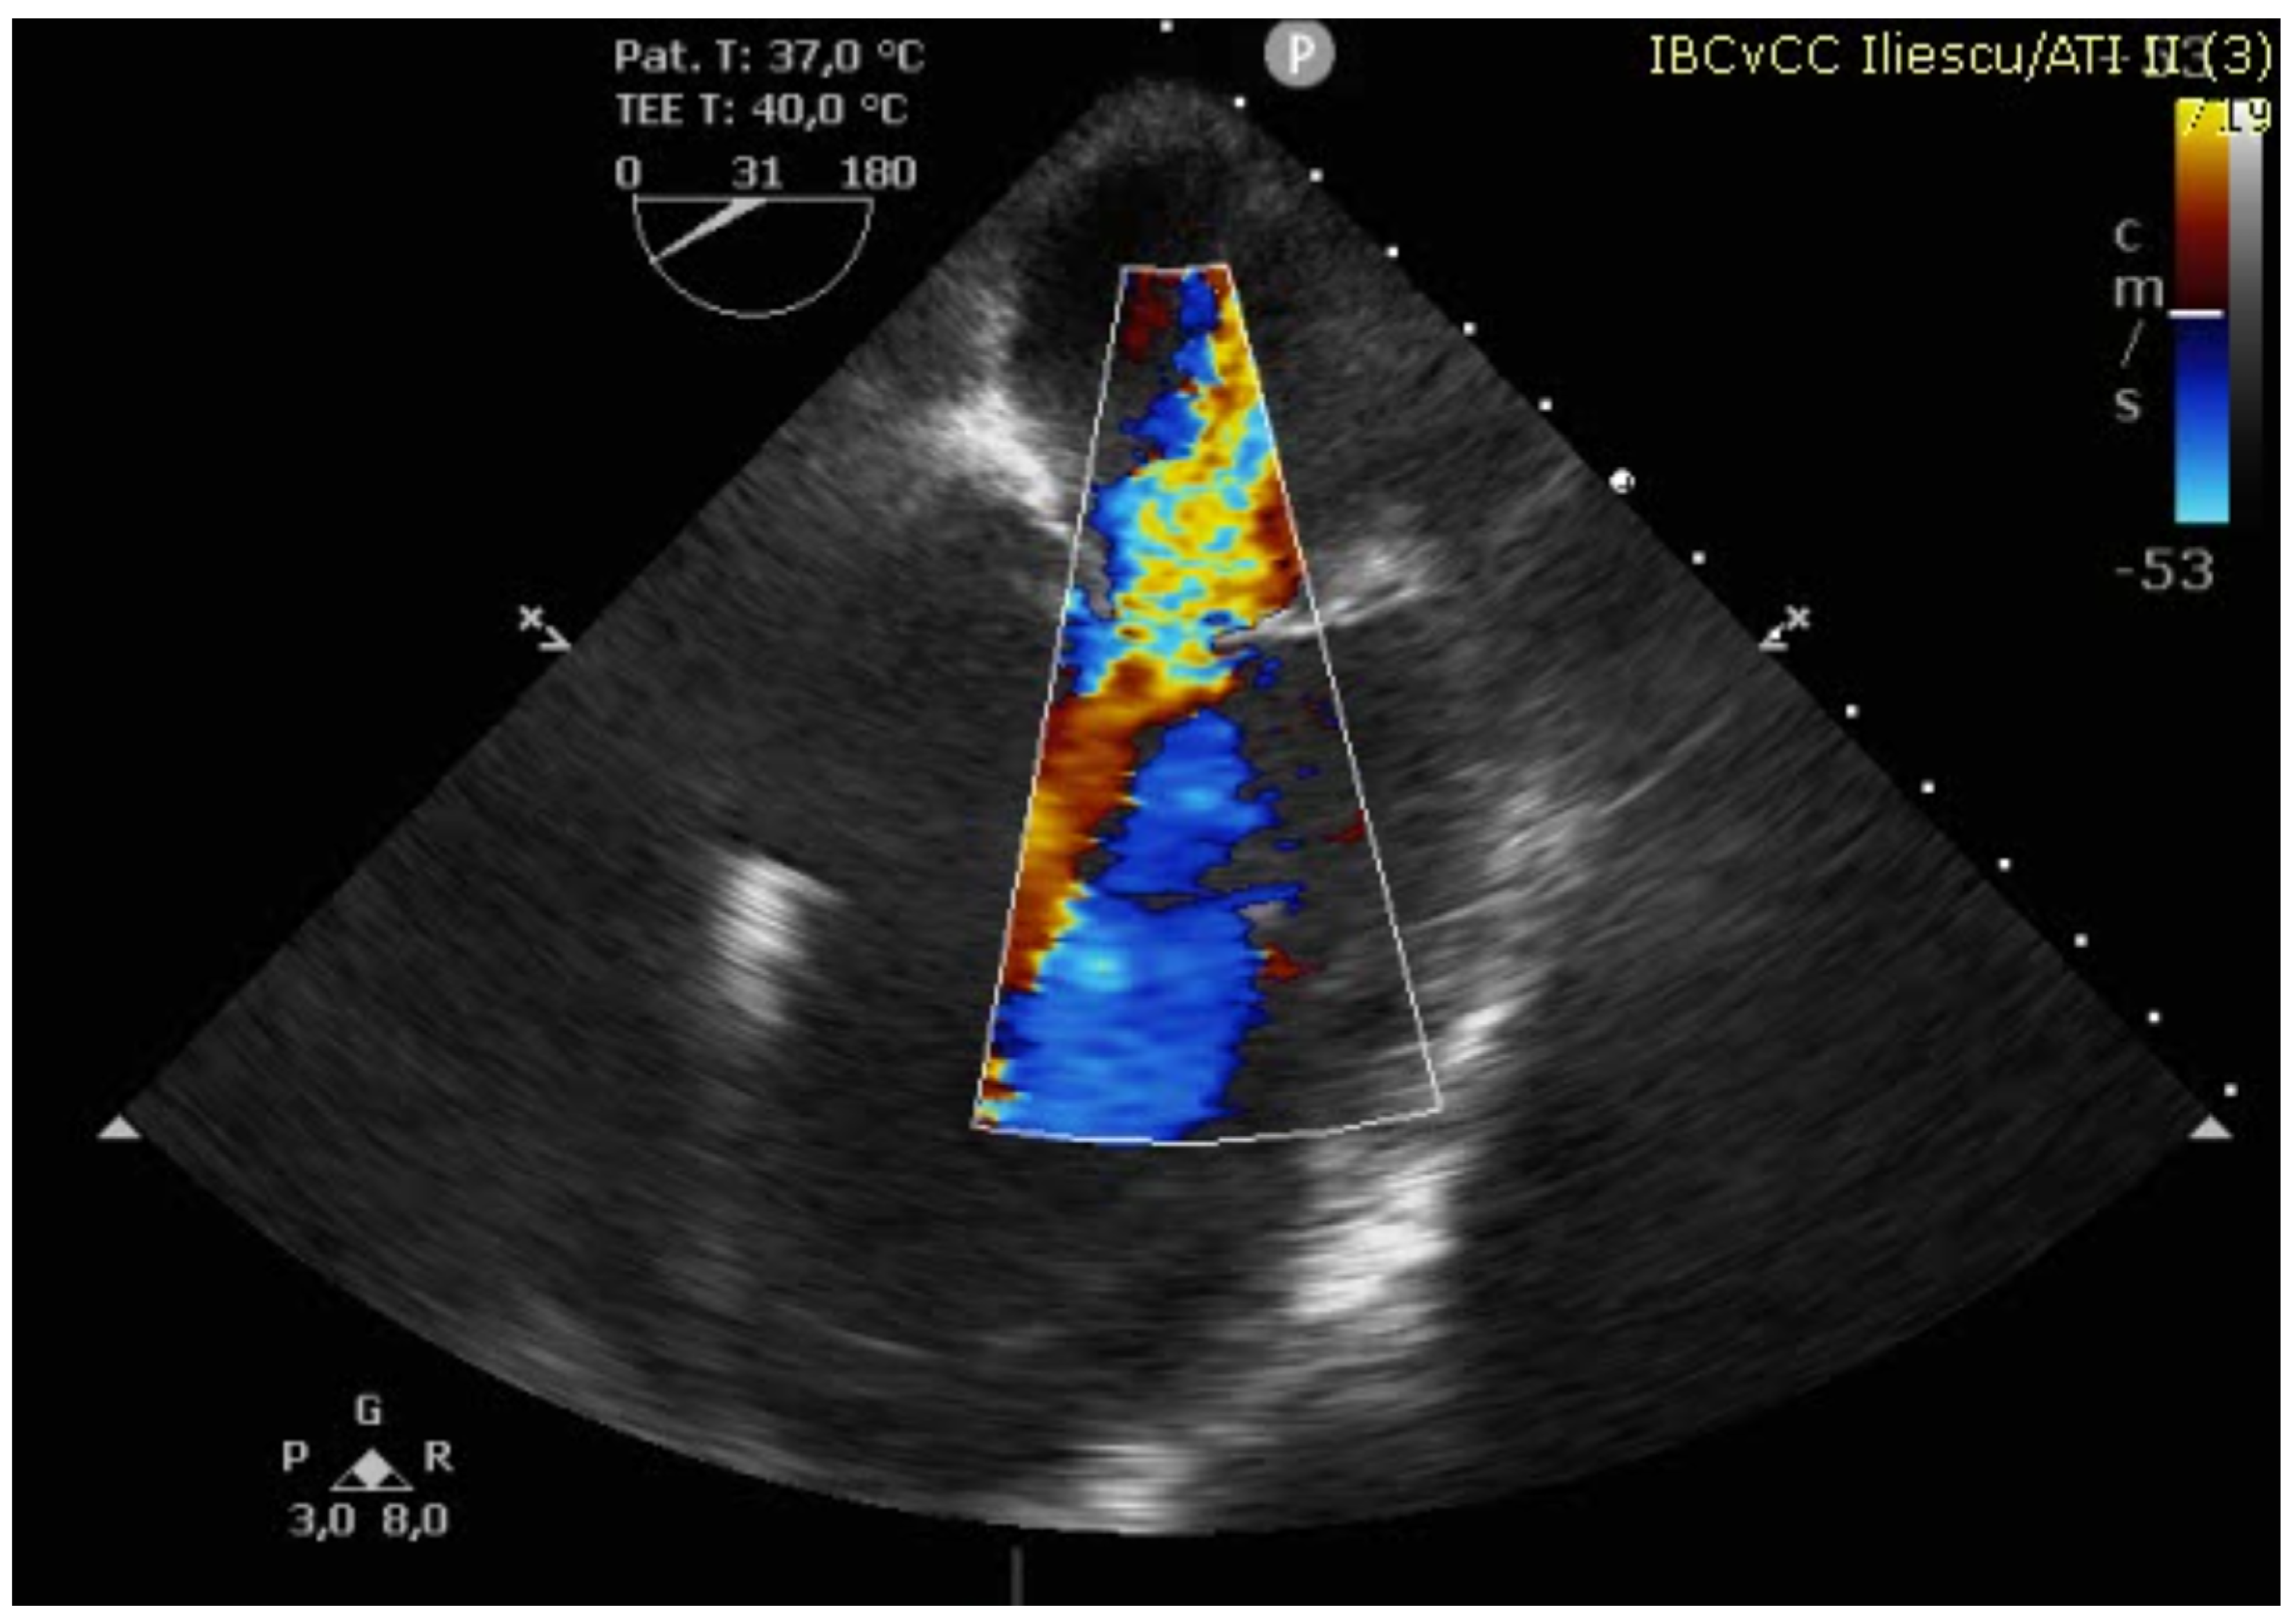

Figure 4. TEE showing severe MR and VSD.

The case was discussed in the multidisciplinary heart team (cardiologist, interventional cardiologist, cardiac surgeon, anesthesiologist) and, after informed consent, it was decided for a watchful waiting tactic, planning a delayed repair. Preoperatively, the patient was evaluated with a transesophageal echocardiography (TEE) for better defect characterization and MR quantification (Figure 3 and Figure 4). Percutaneous defect closure was deemed technically unfeasible due to the anatomy of the defect, which was located at the base of the septum and involved the mitral valve apparatus, while also exhibiting significant mitral valve regurgitation.